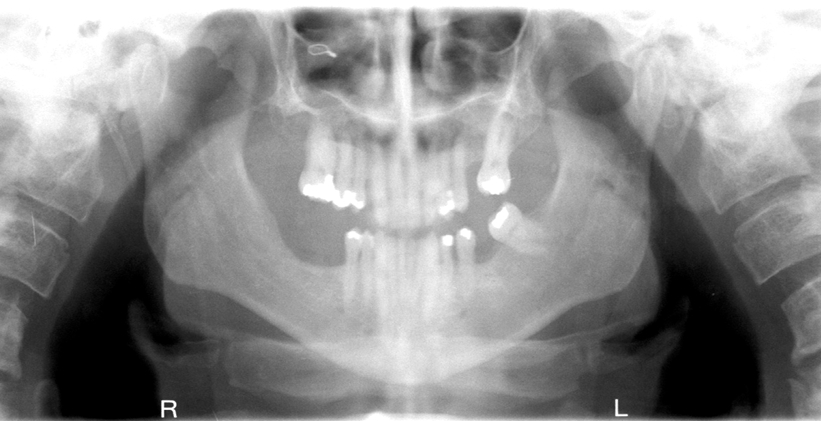

What is wrong with this image?

head turned

unequal magnification of one side; overlaped contacts on ONE side